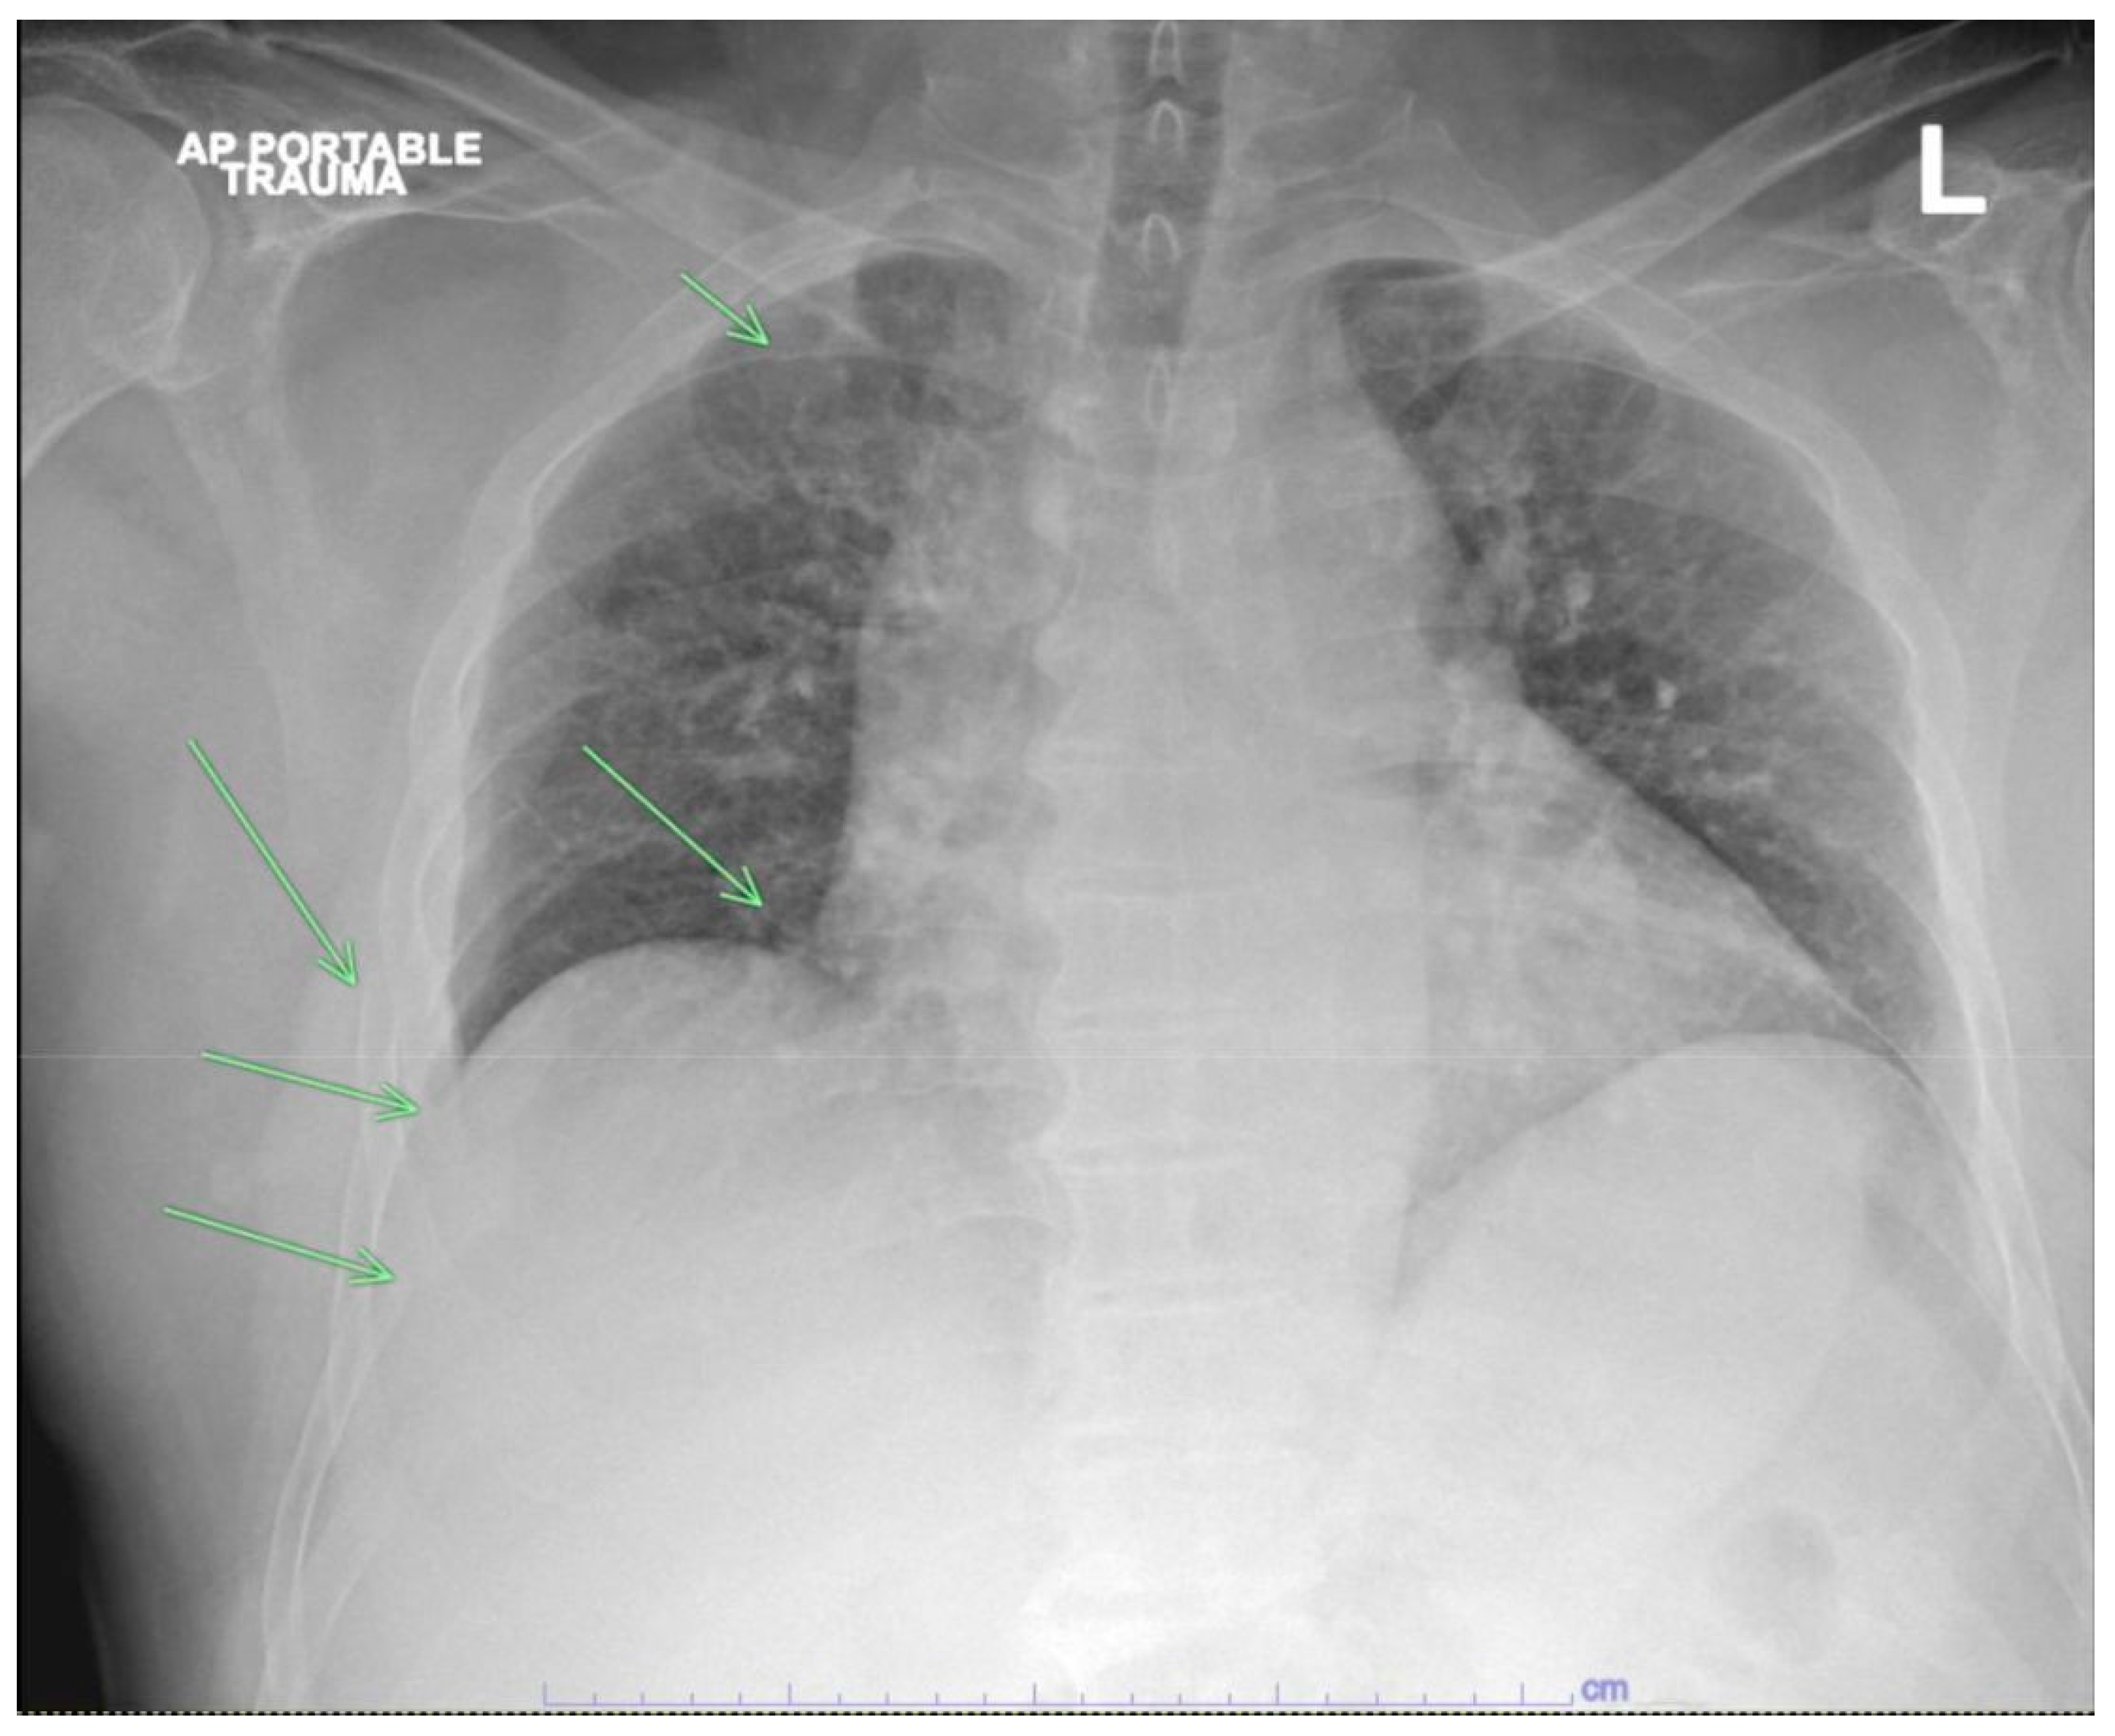

Figure 1. Chest X-ray demonstrating multiple right rib fractures (Green arrows) and mediastinal widening.